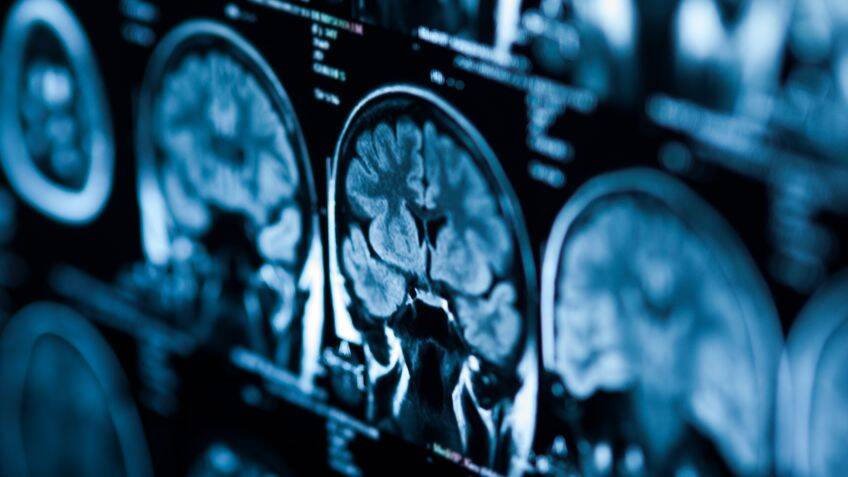

Making MRI scans more accessible By 15th January 2025 An MRI simulator gives students access to vital imaging training without the need for an expensive machine This content is for members only. Please click here to view the full article.